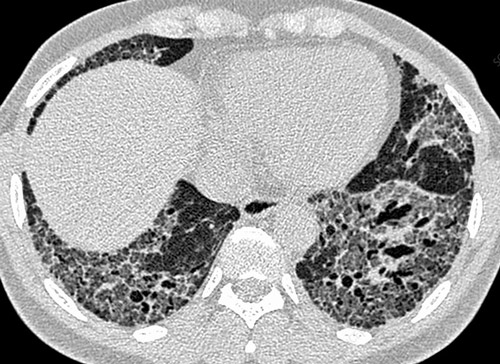

КТ грудной клетки 42-летнего мужчины, больного ревматоидным артритом, с фиброзом легких (рубцеванием легких), вызванным неспецифической интерстициальной пневмонией

Неспецифическая пневмония протекает медленно. В легочной ткани появляются однородные воспалительные изменения, очаги фиброза, отек альвеолярных стенок, скопление внутри экссудата. Больные в течение нескольких лет мучаются от непроходящего кашля и постоянной одышки, усиливающейся по утрам, после физической нагрузки, подъема по лестнице. Эта форма патологии чаще возникает у пожилых лиц и злостных курильщиков. Неспецифическая пневмония может протекать бессимптомно. Пациенты страдают от общей слабости, упадка сил и прочих признаков астенизации. Клинические проявления со стороны дыхательной системы при этом отсутствуют.